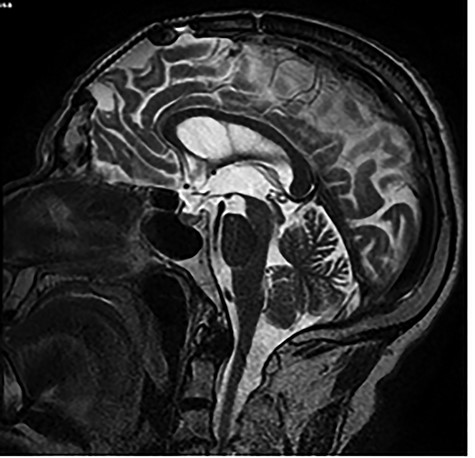

Brain MRI showing titanium cranioplasty without signs of relapse.

and cranioplasty was performed. No clinical or imaging signals of recurrence had been described. We requested a new brain magnetic resonance imaging (MRI) concluding that there was no tumour recurrence (Fig. 3).